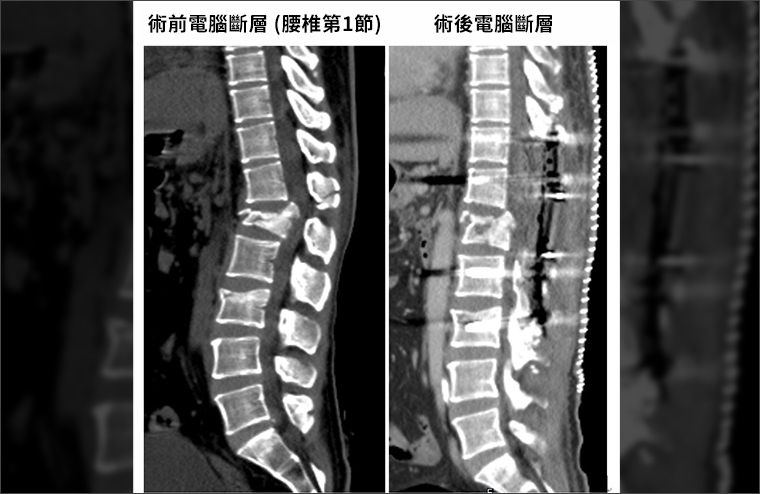

▲手術前腰椎嚴重受損,手術後脊椎固定、神經修復,病人已重返日常生活。(圖/衛生福利部台北醫院提供)

台北醫院多專科跨領域合作,由急診團隊迅速完成專業評估,放射科隨即進行精密檢查,確認損傷位置與範圍。神經外科醫師擬定治療計畫及醫病溝通,再與開刀房團隊把握黃金時間執行「胸椎至腰椎精準神經減壓及內固定術」,成功為病人去除壓迫神經的骨片、血塊組織,矯正拉直壓扁的脊椎骨並重新固定脊椎,幫助受損神經儘快在安全而穩定的情況下修復。